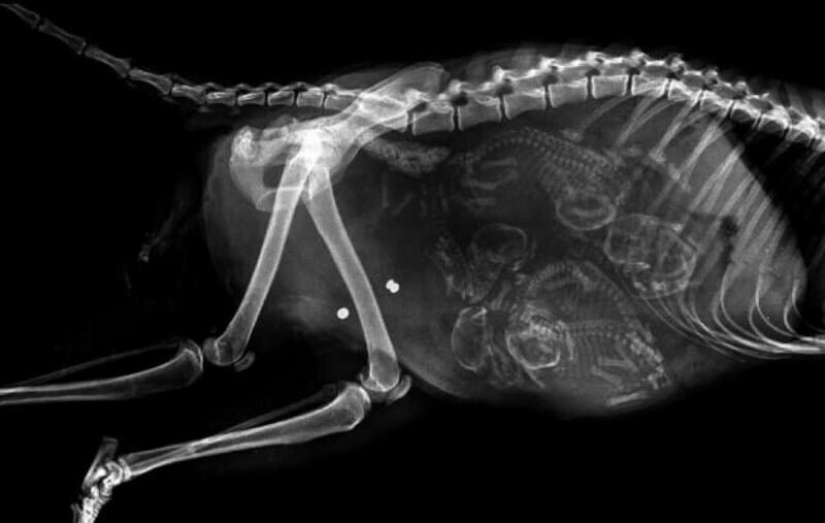

Quién vive en la casita: radiografías de animales preñados

Por Pictolic https://pictolic.com/es/article/quien-vive-en-la-casita-radiografas-de-animales-prenados.html¿Alguna vez te has preguntado qué sucede en el útero de una gata o una perra preñada? ¿Cómo encajan todos estos pequeños bebés allí y logran desarrollarse durante todo el embarazo? La mayoría de los animales preñados se examinan mediante rayos X. Y éstas, cabe señalar, son fotografías muy interesantes.

Especialistas que como parte de su trabajo observan animales que están listos para parir, compartieron estas sorprendentes imágenes de rayos X y ultrasonido.

perra preñada